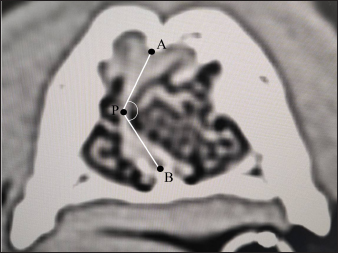

Nasal septum deviation is one of the normal anatomical individual differences (Miles and Schwarz, 2020). The air percentage and contrast enhancement of nasal mucosa in the right and left nasal cavities can change when the nasal septum deviation concentrates nasal structures either on the right or left nasal cavity. In other words, it is difficult to determine whether the changes in patients with nasal septum deviation are caused by nasal inflammation or simple individual differences. Therefore, this study examined the right–left ratio of the air percentage and contrast enhancement in normal dogs with remarkable nasal septum deviation. Chihuahuas and Shih tzus were considered because nasal septum deviation can be easily found in these breeds compared with Miniature dachshunds, Toy poodles, and Shibas. However, since there are no distinct criteria regarding the presence and degree of nasal septum deviation, a standard indicating that “nasal septum deviation is remarkable” was needed in Chihuahuas and Shih tzus. Thus, after measuring the angle of nasal septum deviation in both breeds, dogs whose minor angle sides of nasal septum deviation were median value or less were selected. Based on previous studies (Auger et al., 2016; Miles and Schwarz, 2020), the degree of nasal septum deviation was defined as APB, where (A) is the dorsal point of the nasal septum; (P) is the most deviated point of the nasal septum; and (B) is the ventral point of the nasal septum, which is the binding site of the nasal septum and vomer (Fig. 1). Regarding each dog, transverse sections on which the degree of nasal septum deviation was visually the largest were selected for APB measurement. The CT images reconstructed with bone function were used for measuring APB. The window configurations were as follows: window width 1,500 and window level −300. After measurement, the air percentage was analyzed in eight Chihuahuas and eight Shih tzus whose APB values were median values or less. Since the direction of nasal septum deviation was not always similar, the right and left nasal areas were defined as the major and minor angle sides. After calculating the air percentage on the major and minor angle sides using the method mentioned above, the proportion of the air percentage on the minor angle side to that on the major angle side was calculated. In addition, differences in contrast enhancement were analyzed. However, the post-contrast CT images were not obtained in three Chihuahuas. Therefore, the CT images of six Chihuahuas and eight Shih tzus whose APB values were median value or less were selected. After calculating the contrast enhancement on the major and minor angle sides using the method mentioned above, the proportion of contrast enhancement on the minor angle side to that on the major angle side was calculated.

Fig. 1. CT measurements for ∠APB at the maximum level of nasal septum deviation (axial section). A: the dorsal, B: the ventral, and P: the most deviated point of the nasal septum window width: 1,500, window level: −300.